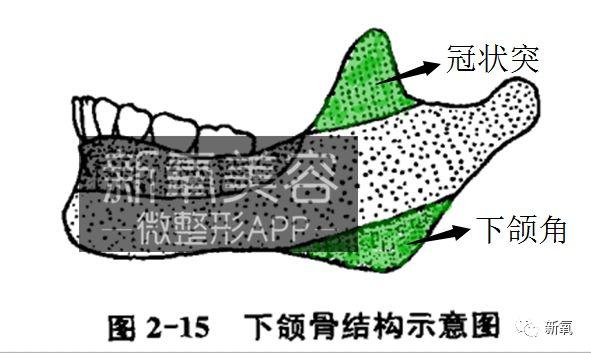

看下图,大家可以简单的理解为,下颌骨原本仅有下图中标黄的管状基础骨体部分。它的生长和一般长骨的生长类似,在发育期两端前后延长。

可是,由于咬肌、翼内肌、以及颞肌等的运动结果,形成了下颌角和冠状突(下图绿色部位)。

觉得好像有点懵的话看这个图。伴随着这个肌肉运动,使得下颌角和冠状突变得明显。

所以如果观察细致的同学会发现初高中时期,爱嚼槟榔的那些男同学(主要是湖南、海南地区),即使原本脸型无比秀气、家里没一个国字脸的··· 依然下颌角日渐增大?

而且还不是单一的咬肌增大,明显可以看到他们一年一年的下颌越来越开,下颌角位置越来越靠下···

因此,在发育期,不要过多的锻炼咬肌除了对脸部软组织线条有好处,对下颌宽度发育也有非常大的好处。

毕竟谁都不想长成低低的下颌角,而是线条、角度都流畅的下颌角。

最后叻,就是这个涂红的位置,因为后来牙齿的萌出形成了这个区域的牙槽突。也就是和今天文章那么多牙齿内容都相关的一个骨体位置啦。

(下颌骨部分的理论依据和骨骼原图来源:《现代口腔正畸学》第四版)